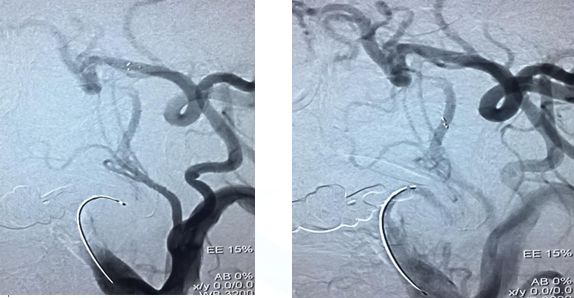

在颈内远端用6*30Solitaire逐次向近端释放支架(夹层可能性大)

支架释放状态血管通畅,逐渐找到血管闭塞部位

支架在病变最近端释放

11-3,21:40:血管再通,支架释放解脱